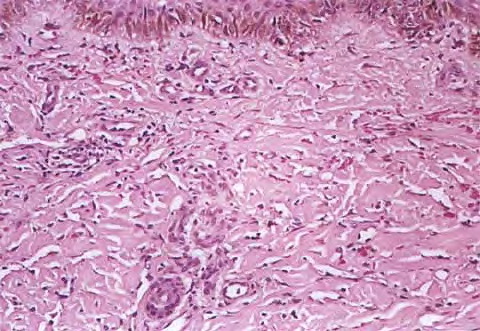

HISTOPATHOLOGY

The histopathology of KS is dependent on the stage of KS development. Early patch-like lesions exhibit rather discrete histopathologic changes, consisting mainly of an increase in the number of dermal vessels, outlined by slightly irregular endothelial cells (Fig. 128-5). These vessels, located mainly in the superficial dermis are parallel to the skin surface, are frequently slightly irregular, and may form bizarre slits and clefts. In the surrounding skin focal hemosiderin, deposits and extravasated erythrocytes can be found as well as a moderate inflammatory infiltrate. Important differential diagnoses of this stage include lymphangioma and granulation tissue.

The pathology of KS plaques is more characteristic and reveals extensive vascular proliferation at all levels of the dermis with multiple dilated and angulated vascular spaces dissecting the collagen leaving a spongy network of collagen tissue. A characteristic sign of KS papules is the presence of solid cords and fascicles of spindle cells arranged between the jagged vascular channels. This biphasic angiomatous and solid tumor morphology changes to a clear-cut sarcomatous morphology with progression of the disease.

Nodular lesions consist predominantly of spindle cells arranged in bundles and interlacing fascicles and interspersed, irregular, slit-like vascular spaces without endothelial linings. Advanced lesions may display pronounced pleomorphism, nuclear atypia, and mitotic figures. At the periphery of solid tumors, (lymph) angiomatous-like portions of KS with bizarre vascular lumina and intravascular and extravasated erythrocytes, as well as siderophages, may be preserved. Erythrocytes, which appear as eosinophilic globules, are trapped within the slits and clefts formed by the spindle cells and erythrophagocytosis are occasionally observed. As in all other stages of KS, a moderate inflammatory infiltrate consisting of lymphocytes, histiocytes, plasma cells, and, sporadically, neutrophils is regularly present.